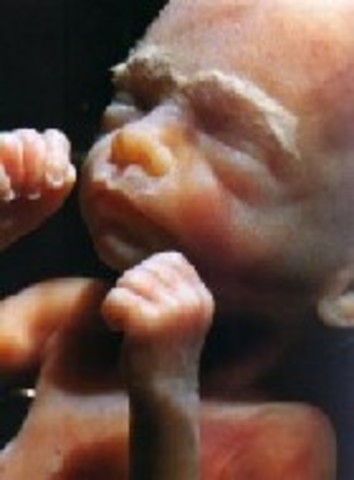

• Week 9: Fingers and Toes form

Week 9: Fingers and Toes form

The fingers and toes are vetu define. The bones atart to form.

• Week Ten: Embryo is now a Fetus

Week Ten: Embryo is now a Fetus

The developing organism is called a fetus.It is the size of a small strawberry.